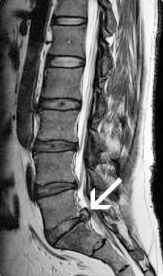

Pe masura ce degenerscenta discala continua, nucleul pulpos se poate rupe de inelul fibros si poate comprima o radacina nervoasa sau chiar sacul dural daca este de dimensiuni mari. Aceasta este considerata o hernie discala si poate cauza durere radiculara, pierderea fortei unei anumite grupe musculare, tulburari senzitive, etc.

Localizarea cea mai frecventa a herniei de disc este la nivelurile L4-L5 si L5-S1 pentru hernia lombara si la nivelurile C5-C6 si C6-C7 pentru hernia de disc cervicala.

- RMN-ul este examenul cel mai pertinent